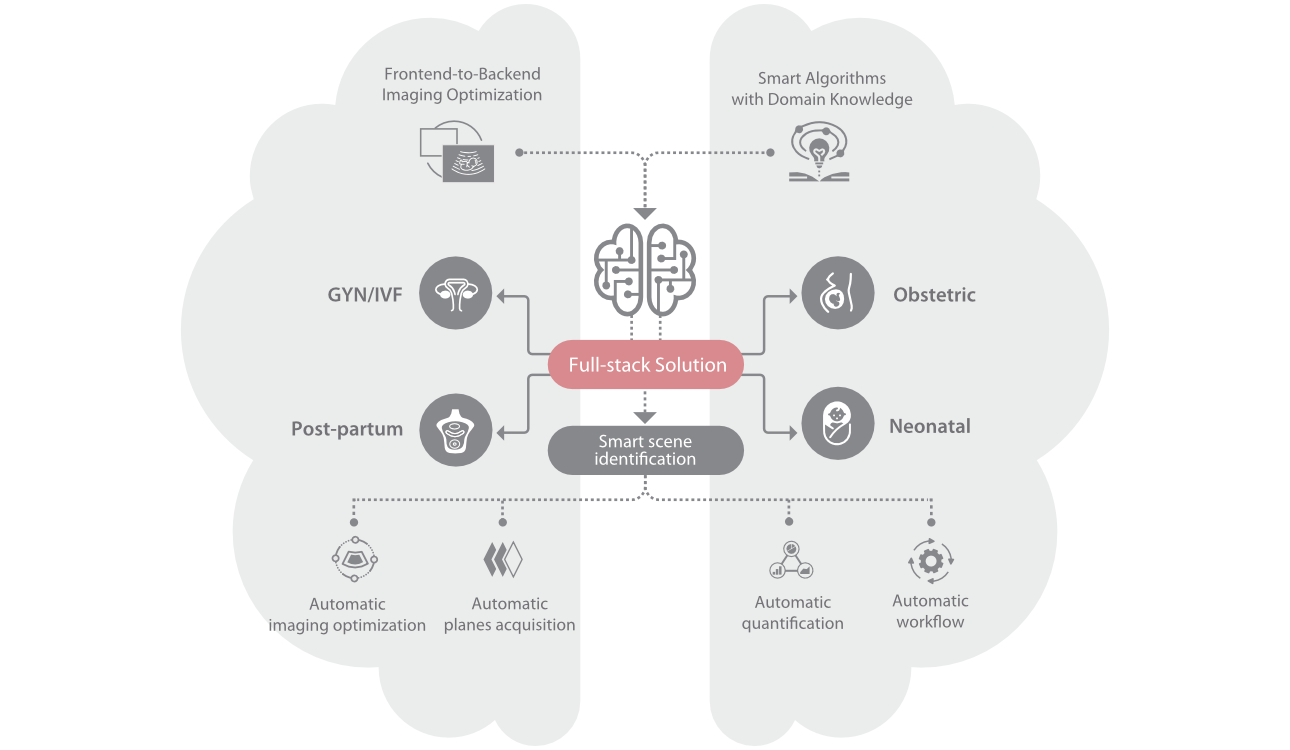

Le Nuewa?I9, con?u spÃĐcialement pour la santÃĐ de la femme et les soins nÃĐonataux, offre une expÃĐrience entiÃĻrement nouvelle gr?ce aux innovations dont il est dotÃĐ, tant à lâintÃĐrieur quâà lâextÃĐrieur. Ces innovations sont dÃĐveloppÃĐes sur la base d'une comprÃĐhension approfondie de scÃĐnarios cliniques complexes, fournissant des rÃĐponses prÃĐcises et adaptÃĐes ainsi qu'une efficacitÃĐ exceptionnelle et une expÃĐrience utilisateur remarquable.

Solution complÃĻte gr?ce au ZST +

La plate-forme ZST+?est une innovation extraordinaire, reprÃĐsentant une ÃĐvolution de lâimagerie ultrasonore. Elle transforme la formation conventionnelle de faisceaux en un traitement basÃĐ sur les canaux de donnÃĐes. Elle repousse les limites de lâimagerie conventionnelle et du compromis entre rÃĐsolution spatiale, rÃĐsolution temporelle et uniformitÃĐ tissulaire en offrant une qualitÃĐ dâimage exceptionnelle pour des solutions dâimagerie infinies et en constante ÃĐvolution.